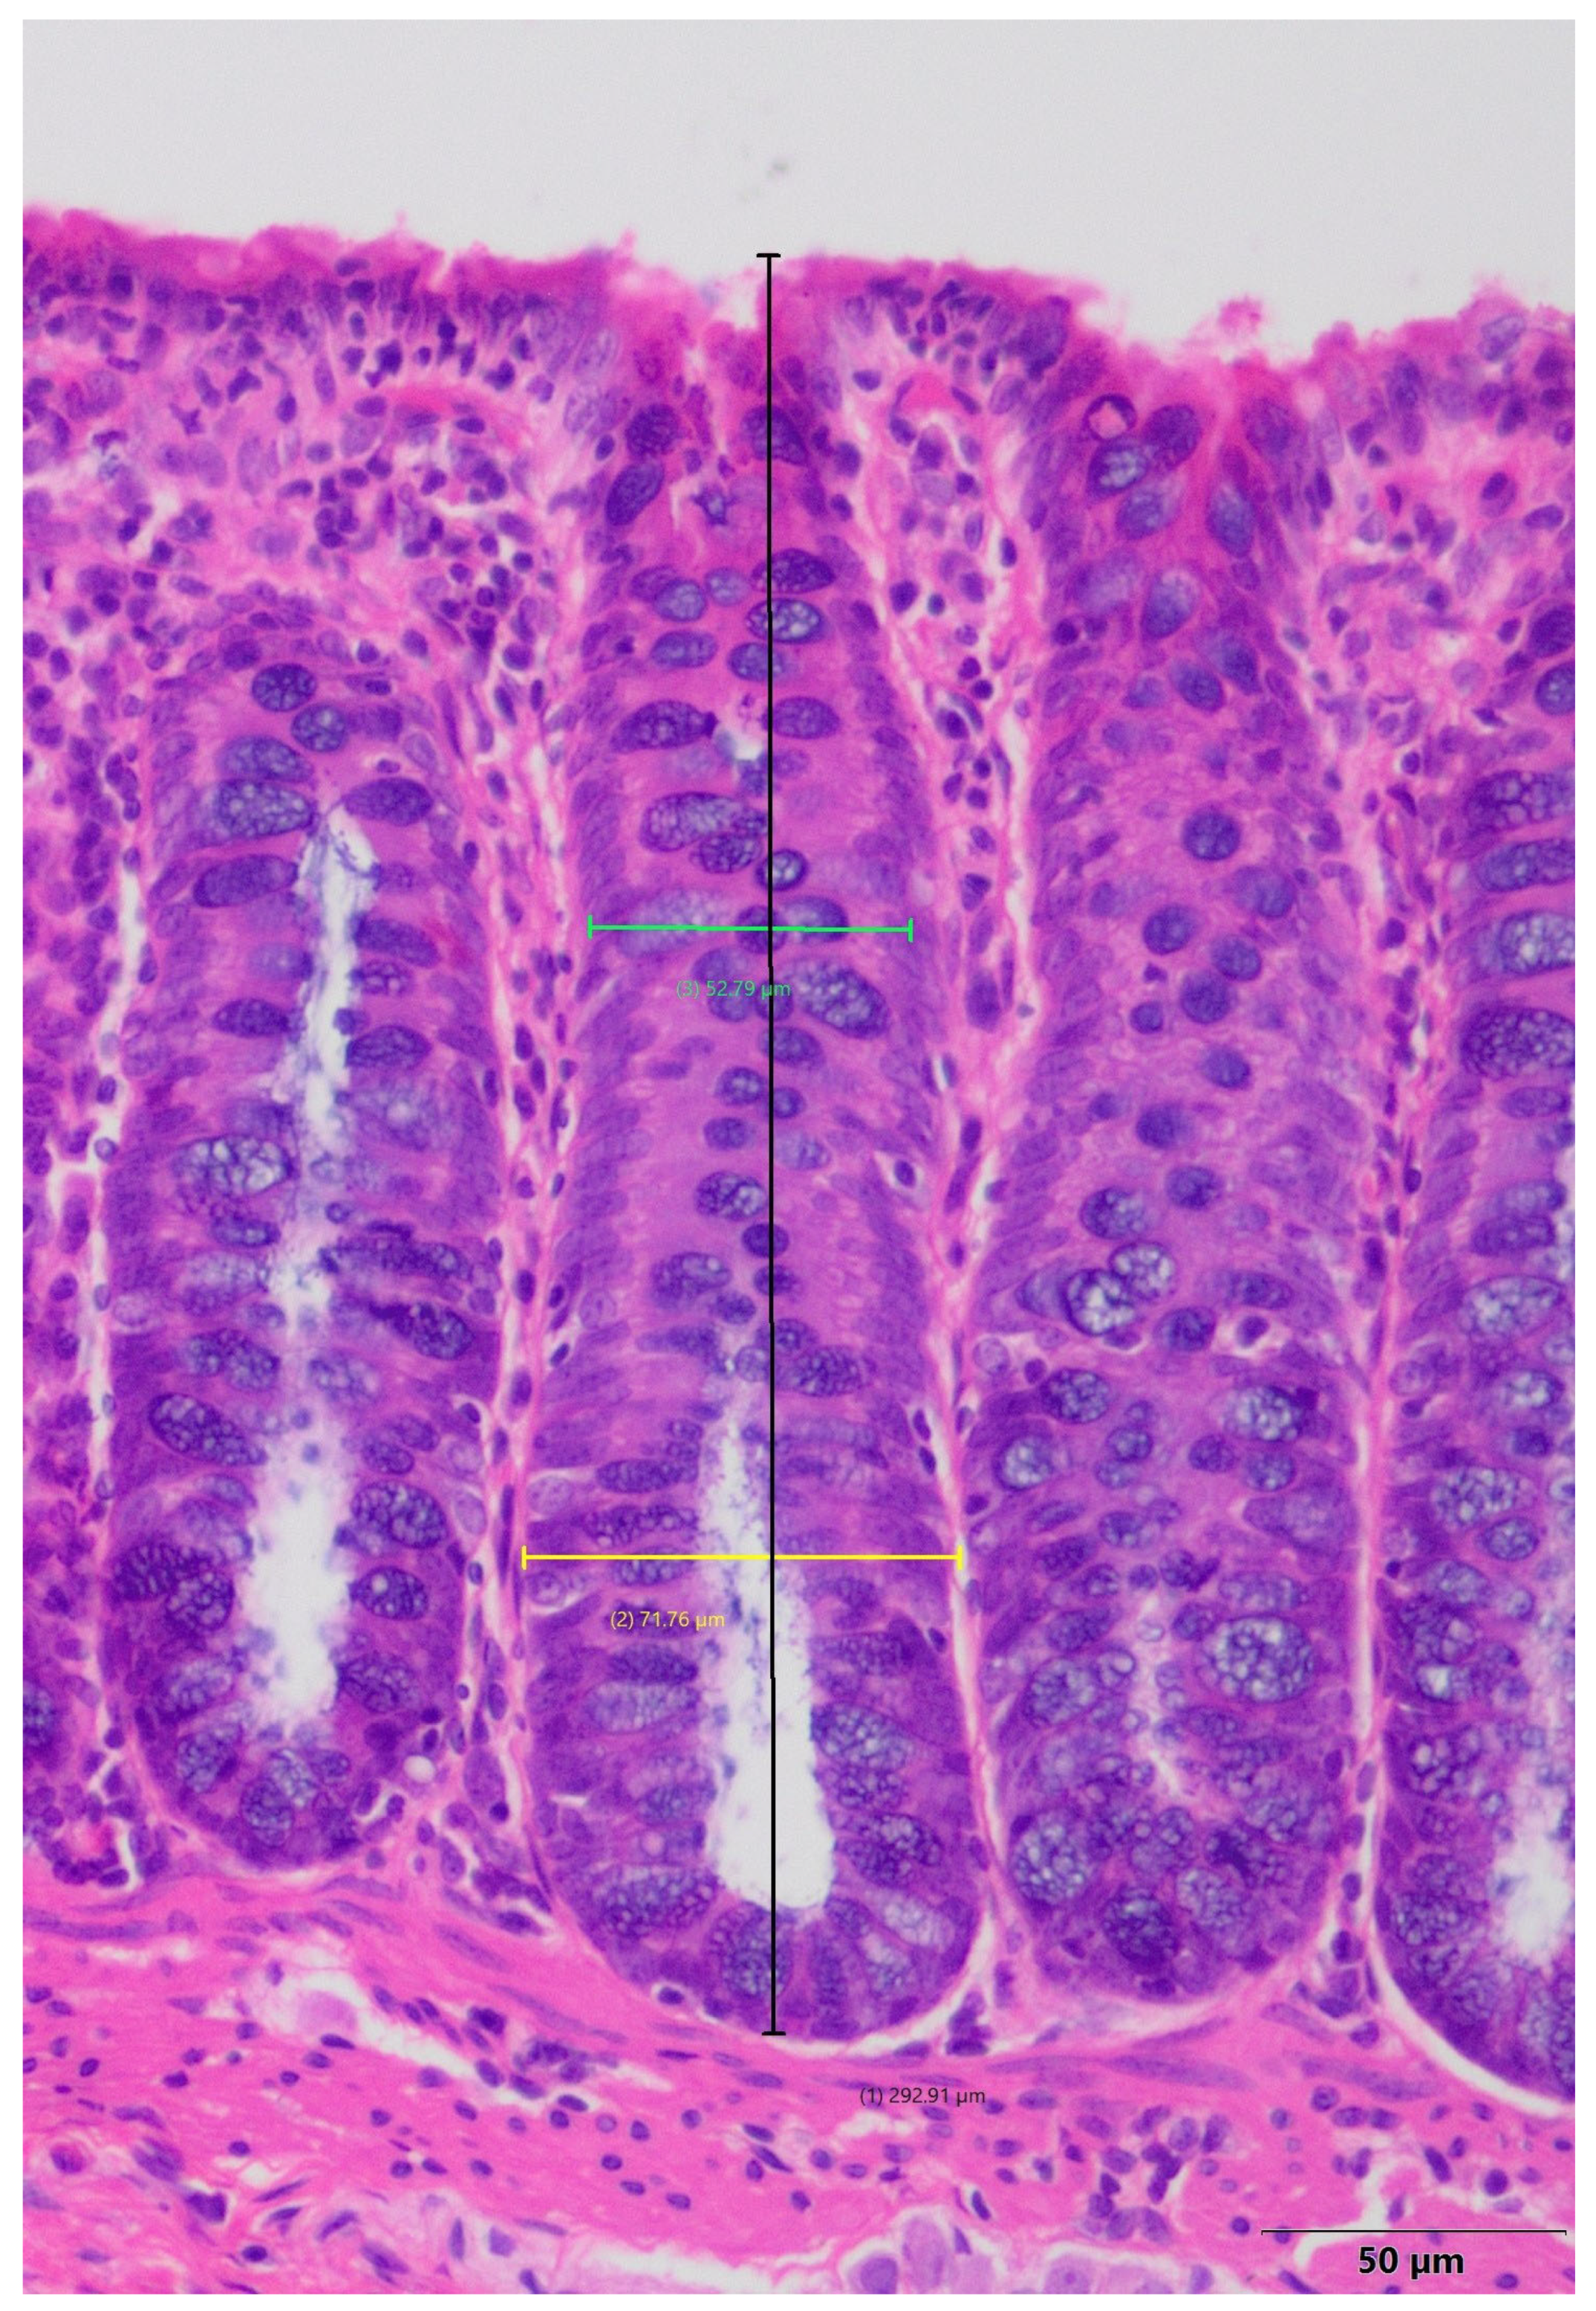

2.7. Histomorphometric Analysis of the Small Intestine

| Parameter/Group | Control Group | Colitis Group |

| Duodenum | ||

| Villus length [μm] | 1128.11 ± 10.92 | 1104.64 ± 12.60 |

| Mucosa thickness [μm] | 935.19 ± 4.52 | 910.66 ± 14.24 |

| Crypt depth [μm] | 320.26 ± 3.46 | 311.73 ± 4.00 |

| Muscularis thickness [μm] | 653.15 ± 3.71 | 642.64 ± 8.72 |

| Proximal Jejunum | ||

| Villus length [μm] | 984.01 ± 6.32 | 993.55 ± 15.92 |

| Mucosa thickness [μm] | 914.42 ± 5.70 | 903.10 ± 10.75 |

| Crypt depth [μm] | 254.78 ± 2.48 | 252.70 ± 2.83 |

| Muscularis thickness [μm] | 594.75 ± 7.55 | 577.00 ± 12.66 |

| Middle Jejunum | ||

| Villus length [μm] | 949.42 ± 6.59 | 941.34 ± 16.94 |

| Mucosa thickness [μm] | 842.68 ± 9.78 | 831.30 ± 7.53 |

| Crypt depth [μm] | 250.91 ± 1.69 | 250.15 ± 3.53 |

| Muscularis thickness [μm] | 568.00 ± 5.48 a | 559.31 ± 9.70 b |

| Distal Jejunum | ||

| Villus length [μm] | 916.30 ± 7.19 | 907.15 ± 9.37 |

| Mucosa thickness [μm] | 812.72 ± 6.88 | 805.45 ± 12.62 |

| Crypt depth [μm] | 249.25 ± 2.29 | 246.12 ± 3.24 |

| Muscularis thickness [μm] | 534.41 ± 3.89 | 530.36 ± 5.19 |

| Ileum | ||

| Villus length [μm] | 864.32 ± 7.64 | 851.66 ± 12.93 |

| Mucosa thickness [μm] | 760.08 ± 6.56 | 738.85 ± 10.23 |

| Crypt depth [μm] | 236.38 ± 2.14 a | 229.16 ± 2.30 b |

| Muscularis thickness [μm] | 521.55 ± 3.68 a | 503.71 ± 6.29 b |